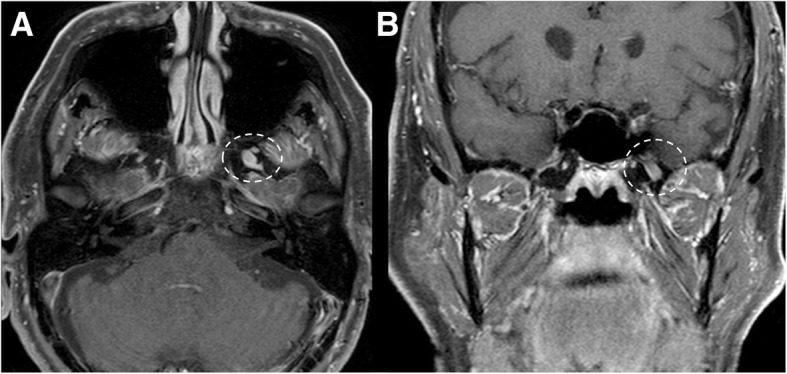

Fig. 12.

Small trigeminal schwannoma. MRI T1-weighted post-gadolinium axial (a) and coronal (b) images show a homogeneous enhancing mass in the right Meckel’s cave (dotted circles)